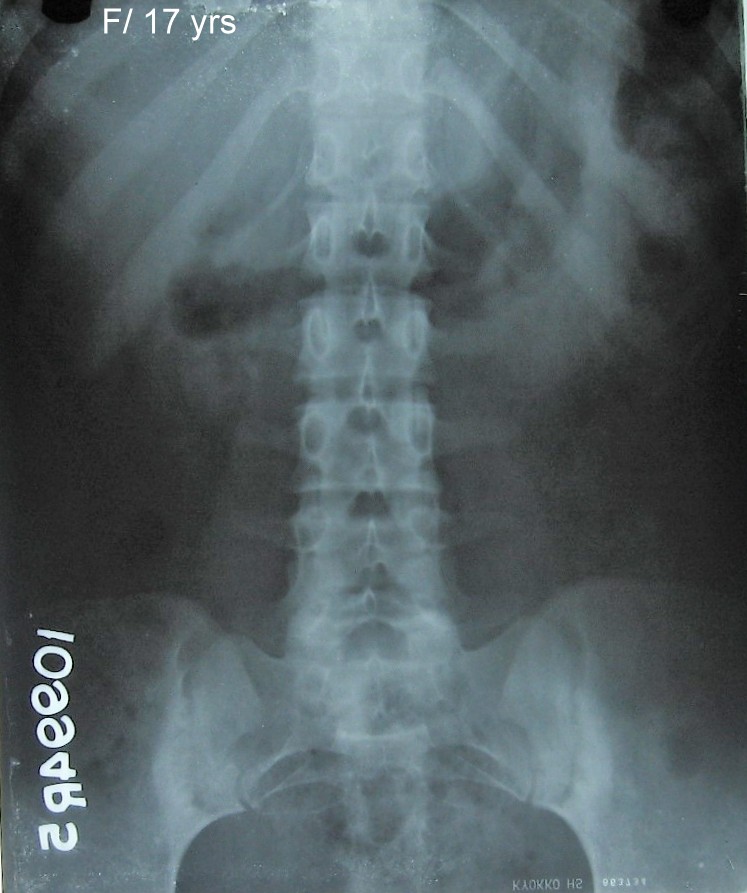

Fig: 1 Lumbar spine A.P with upper pelvis